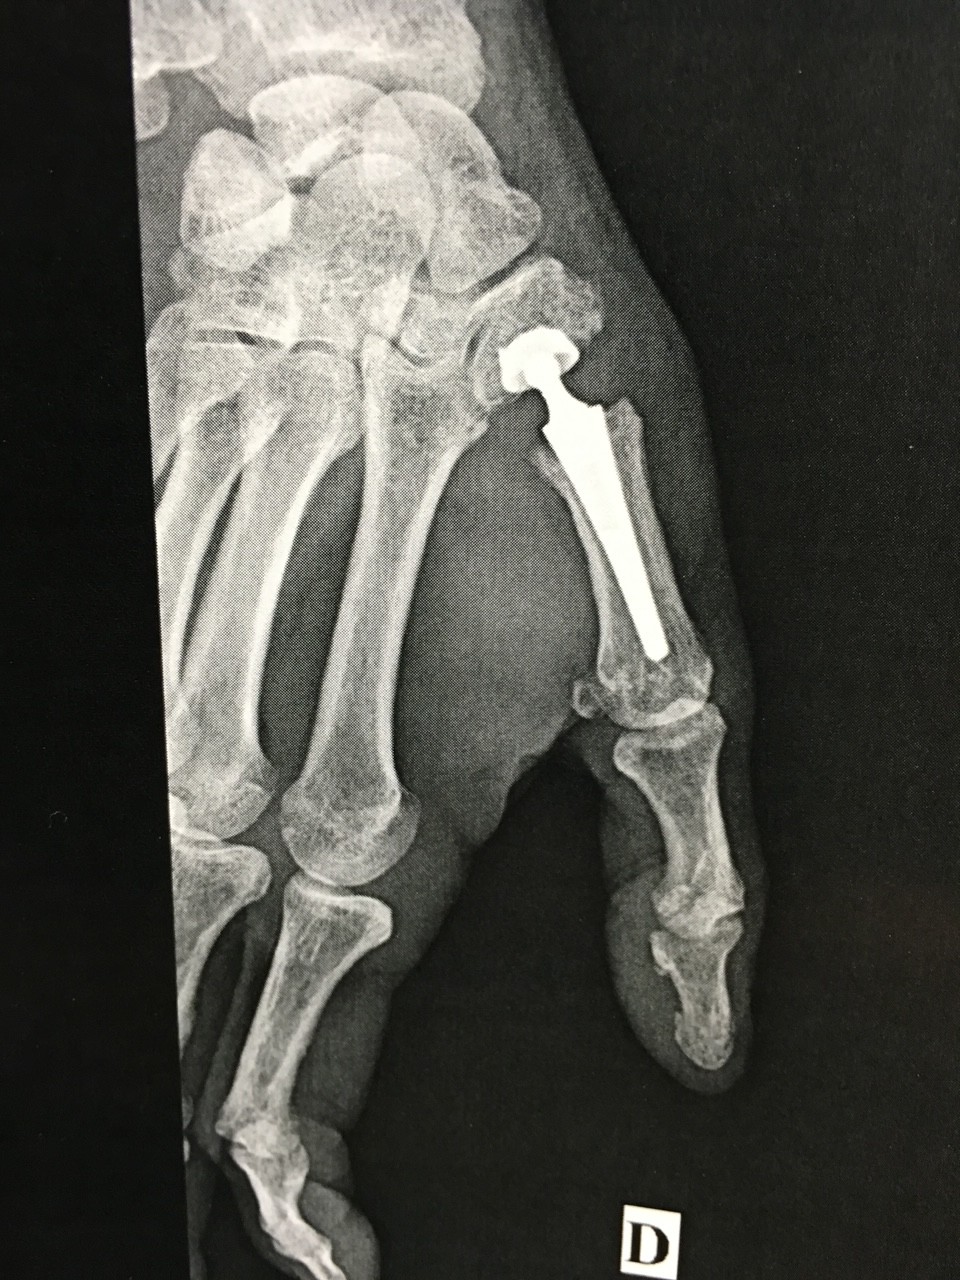

-Le remplacement par une prothèse (arthroplastie)

Chaque opération a ses avantages et ses inconvénients, chaque cas est particulier. L’opération dont il est le plus facile de se remettre est l’implantation d’une prothèse totale qui permet de retrouver une bonne fonction mais elle n’est pas possible en cas de déformation très importante. Le choix de l’opération se fait avec le chirurgien en fonction de vos habitudes de vie, de votre demande fonctionnelle et en fonction de paramètres médicaux.